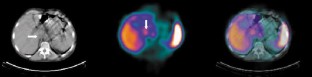

Delayed liver single-photon emission computed tomography (SPECT) after 99mTc red blood cell (RBC) labelling is helpful in detecting hepatic haemangiomas; however, diagnosis can be difficult when lesions are situated adjacent to structures like the inferior vena cava, the heart or hepatic vessels, where blood activity persists. The aims of this study were to evaluate the usefulness of RBC SPECT and transmission computed tomography (RBC SPECT/CT) performed simultaneously with a hybrid imaging system for correct characterisation of hepatic lesions in patients with suspected haemangioma, and to assess the additional value of fused images compared with SPECT alone. Twelve patients with 24 liver lesions were studied. The acquisitions of both anatomical (CT) and functional (SPECT) data were performed during a single session. SPECT images were first interpreted alone and then re-evaluated after adding the transmission anatomical maps. Image fusion was successful in all patients, with perfect correspondence between SPECT and CT data, allowing the precise anatomical localisation of sites of increased blood pool activity. SPECT/CT had a significant impact on results in four patients (33.3%) with four lesions defined as indeterminate on SPECT images, accurately characterising the hot spot foci located near vascular structures. In conclusion, RBC SPECT/CT imaging using this hybrid SPECT/CT system is feasible and useful in the identification or exclusion of suspected hepatic haemangiomas located near regions with high vascular activity.

Fig. 1

Fig. 2